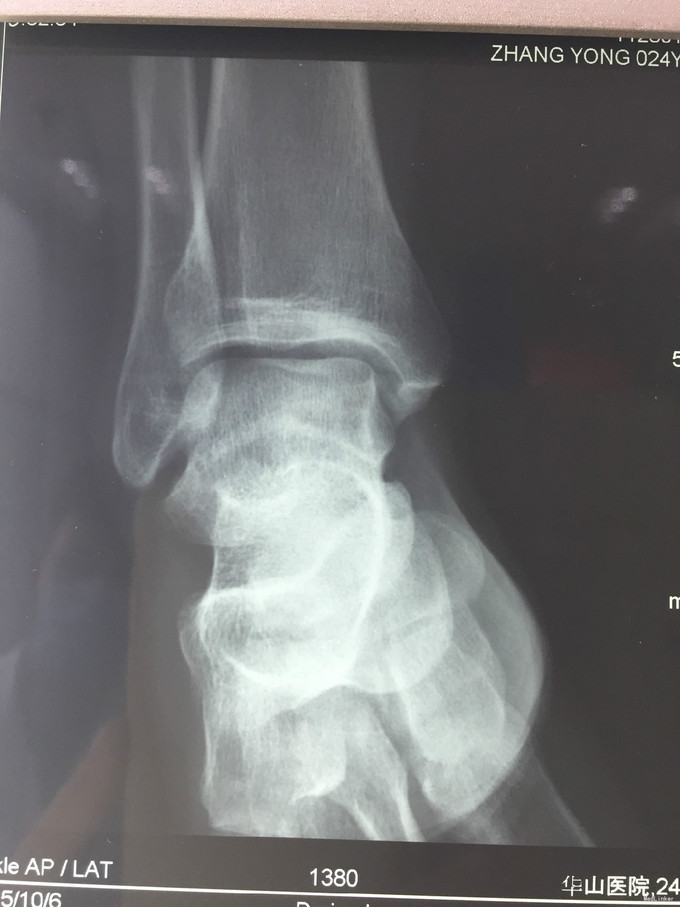

主诉:右踝扭伤后疼痛3年,伴活动受限2年。 现病史:患者男性,24岁。3年前,患者运动时扭伤右踝,无出血。患者当时至外院就诊,予消炎药物保守治疗,疼痛缓解。2年余前患者出现右踝活动受限,以背屈受限明显,伴右踝疼痛,无发热、盗汗,无其它关节痛,无晨僵等。2年来患者自觉右踝疼痛及活动受限症状逐渐加重。外院查MRI示:右胫骨远端前方骨质增生、右距骨前方骨性隆起、右踝关节内积液。我院查右踝X线示:右距骨前下方骨质密度增高、右胫骨前缘骨质增生。于我院就诊,门诊拟"右踝前方撞击综合征、右距骨骨软骨瘤、右踝滑膜炎"收入院。

查体:左下肢、双上肢肌力及活动度正常。右腓肠肌稍萎缩,右踝无明显肿胀。右踝关节跖屈、背屈受限,右踝内侧及前方关节间隙压痛(+)。ADT(-),下蹲提踵试验(+),内翻试验(-)。右腓肠肌肌力、肌张力、感觉正常。 辅查:见现病史。图片见下。

入院诊断:右踝前方撞击综合征、右距骨骨软骨瘤、右踝滑膜炎 治疗:入院完善术前检查后行右踝关节镜下滑膜清理+前方撞击成形+距骨骨软骨瘤切除。